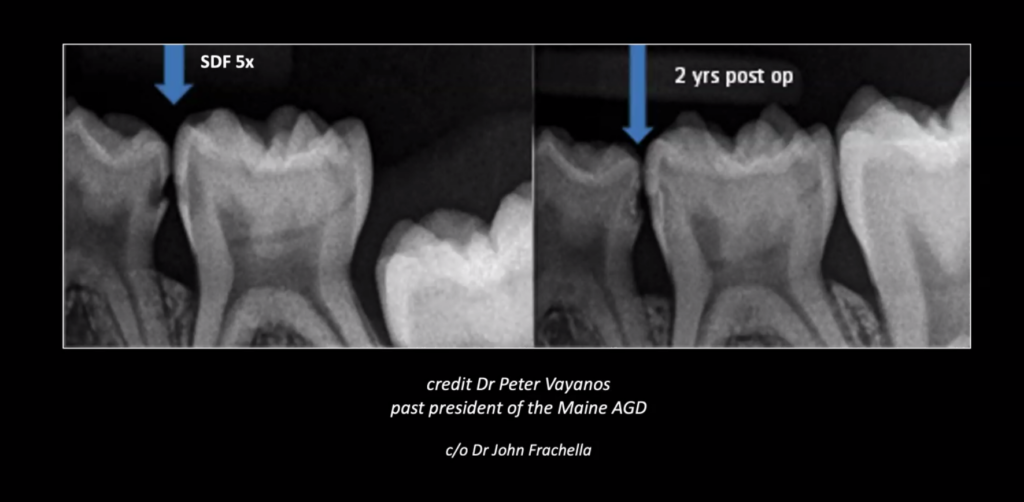

Silver Diamine Fluoride (SDF) is a liquid treatment used to stop cavities from progressing and to help with tooth sensitivity. It helps strengthen the tooth and targets the bacteria that cause decay. SDF is safe, quick, and painless. It is gently brushed onto the affected area and only takes up to one minute to apply.

One important thing to know is that SDF permanently stains the area of decay where it is placed. This color change shows that the cavity has been treated.

One method Dr. Rayna Strong uses is called “SMART” (Silver Atraumatic Restorative Treatment). SMART begins by applying SDF to stop cavities and reduce sensitivity. The tooth is then restored with a biocompatible, tooth-friendly material, such as glass ionomer, helping protect the tooth without drilling or discomfort.